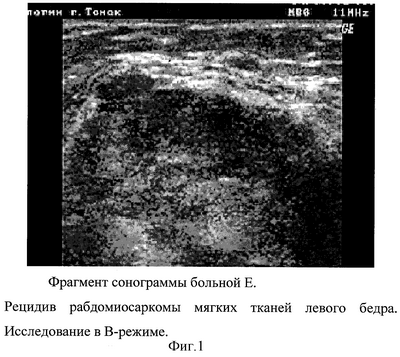

Пациентка Е., 73 года. Из анамнеза: в 2001 году выполнено широкое иссечение саркомы мягких тканей левого бедра с интраоперационной лучевой терапией 20 Гр. Через 3 года после операции отметила появление уплотнения в области послеоперационного рубца, которое значительно увеличилось в размерах за последний месяц. При осмотре в верхней трети левого бедра в области послеоперационного рубца определяется опухолевидное образование размерами 90×60 мм, тугоэластичной консистенции, болезненное. При исследовании предлагаемым способом в проксимальном отделе послеоперационного рубца по медиальной поверхности левого бедра определяется объемное мягкотканое образование размерами 57×35 мм пониженной эхогенности неравномерно неоднородной структуры, содержащей анэхогенные включения и выраженную собственную сосудистую сеть. Контуры узла бугристые, нечеткие. Сосудистый пучок бедра располагается кпереди от образования. В медиальных отделах левой паховой складки имеет место аналогичный узел 10×8×15 мм. При ЦДК в рецидивном узле визуализируются множественные мелкие извитые собственные сосуды, что соответствует степени васкуляризации 3 балла, преимущественно в периферических отделах (см. фиг.1 и 2). Окружающие опухоль ткани имеют повышенную эхогенность, структура их сглажена. Эхоскопическое заключение – рецидив саркомы мягких тканей.

Произведено широкое иссечение опухоли. Гистологическое заключение – рецидив рабдомиосаркомы, что подтверждают данные ультразвукового исследования.